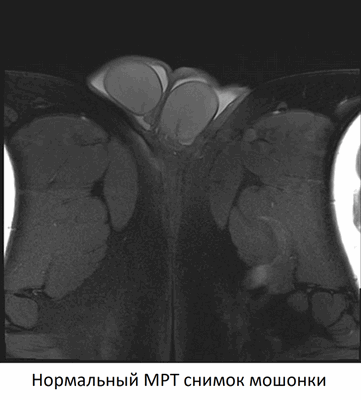

Нормальные яички. МРТ: (а) Аксиальное Т2-взвешенное изображение. Нормальная интенсивность сигнала от яичек; (b) Сагиттальное Т1 -взвешенное изображение после внутривенного введения контрастного вещества. Сигнал средней интенсивности от яичка. Нормальный хвост придатка (стрелка).

Что покажет МРТ при нормальной мошонке

- гомогенный сигнал средней интенсивности на Т1-взвешенном изображении

- Высокая интенсивность сигнала на Т2-взвешенном изображении

- Гипоинтенсивная перегородка идет радиально от капсулы к средостению яичка

- Белочная оболочка: тонкая линия с низкой интенсивностью сигнала

- изоинтенсивный по сравнению с яичками на Т1- взвешенном, гипоинтенсивный на Т2-взвешенном изображении

- более выраженное контрастное усиление по сравнению с яичками.